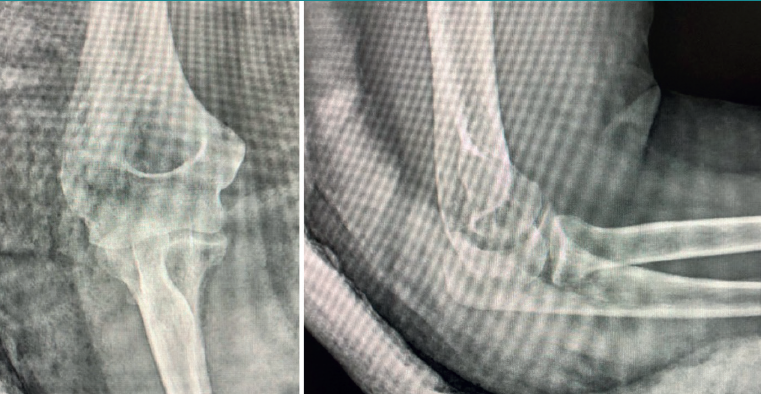

A 53-year-old woman with no relevant personal history suffered a fall with trauma of the right elbow and ankle. The patient described the fall as occurring with the shoulder raised and the elbow extended and in supination. She suffered functional impairment of the elbow, with posterior deformity of the latter. In the emergency service and following physical examination and radiographs, the patient was diagnosed with posterior dislocation of the elbow with impact fracture in the posterior region of the lateral condyle, in addition to subtalar luxation. The elbow dislocation was reduced that same day, exerting downward traction over the forearm with the elbow in 90º flexion, and with immobilisation by means of a posterior arm splint. After three weeks the patient was examined in the outpatient clinic and the splint was removed. She then started 8 weeks of rehabilitation, with a rapid gain of joint balance (0-120º).

The patient was again evaluated in the clinic after 12 weeks. The physical examination revealed pain on the lateral aspect of the right elbow, with clicks on pronation, positive pivot shift manoeuvre and painful varus laxity. Complementary tests were requested: radiographs, which evidenced the Osborne-Cotterill lesion (Figure 1); a magnetic resonance imaging (MRI) scan showing distal deinsertion of the ulnar lateral collateral ligament and proximal deinsertion of the radial collateral ligament, as well as partial rupture of the annular ligament; and a computed tomography (CT) scan that found the Osborne-Cotterill osteochondral defect in the posterior capitellum to measure 8 × 3 mm (Figure 2). The patient suffered another posterior dislocation episode the following week after a new fall while undergoing rehabilitation. A second closed reduction was therefore performed.